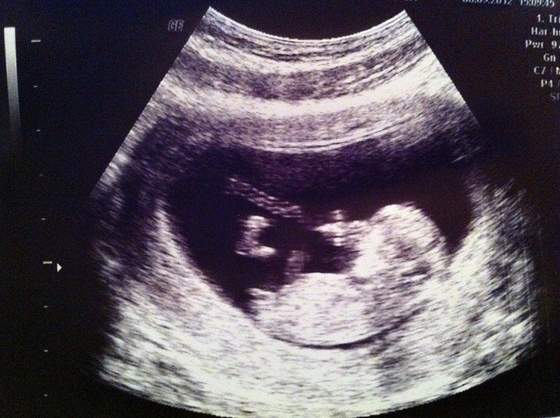

Ewelinka, to jest tzw nub i na tym etapie maja go i chlopcy i dziewczynki:-) Twoj z kata nachylenia jest bardziej dziewczynkowy, ale ksztalt juz nie taki jednoznaczny... Wiec pewnie dowiesz sie pozniej kto tam mieszka;-)